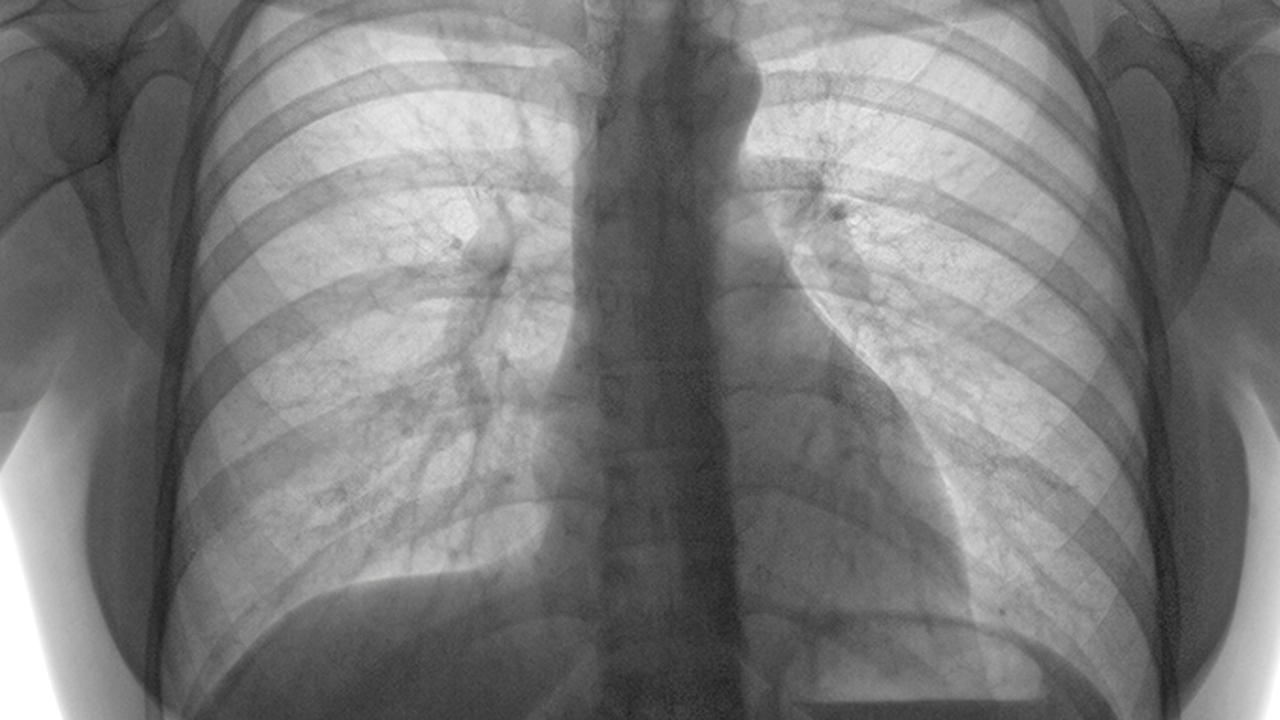

肺结节是肺部常见的影像学表现,病因复杂多样,可能与感染、炎症、肿瘤等因素相关。早期发现和规范诊疗对预后至关重要。